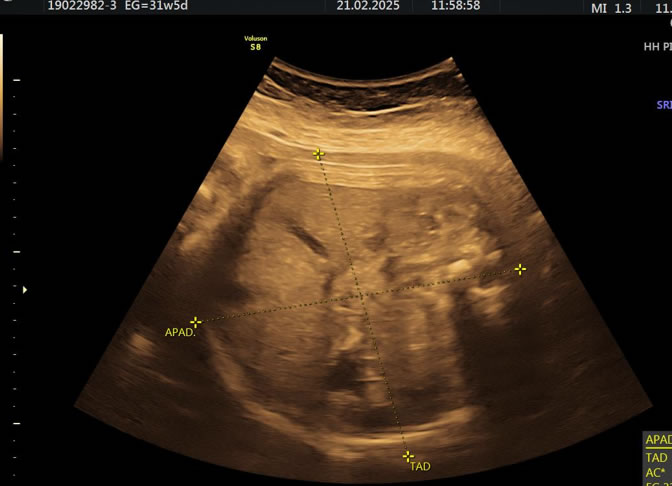

• Eco Doppler III Trimestre